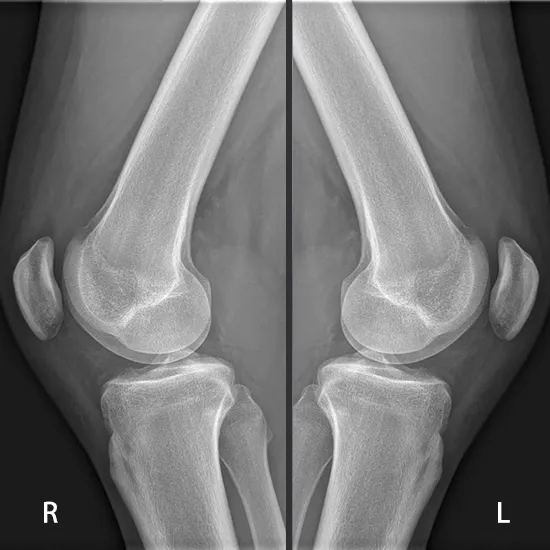

X-Ray Both Knee LAT View

Knee X-rays are an imaging tool used to evaluate the knee joint's alignment, bone quality, and the number of degenerative changes. Lateral (LAT) images are obtained by positioning the X-ray beam perpendicular to the patient.